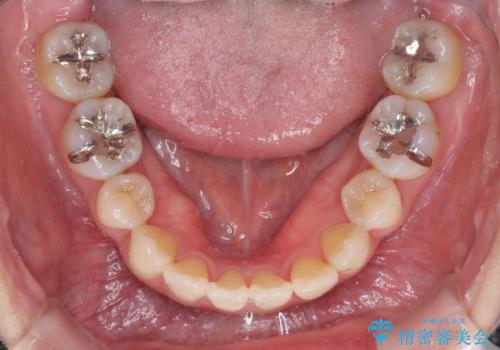

- 下顎の歯が舌側に倒れていることと、前歯の咬み合わせの不具合を気にして来院された患者様です。

受け口傾向の口元であるため、下顎左右小臼歯各1歯を抜歯して歯列を整えることとしました。

前歯には治療中の仮歯が装着されていたため、矯正治療後にオールセラミッククラウンにて補綴治療を行うこととしました。